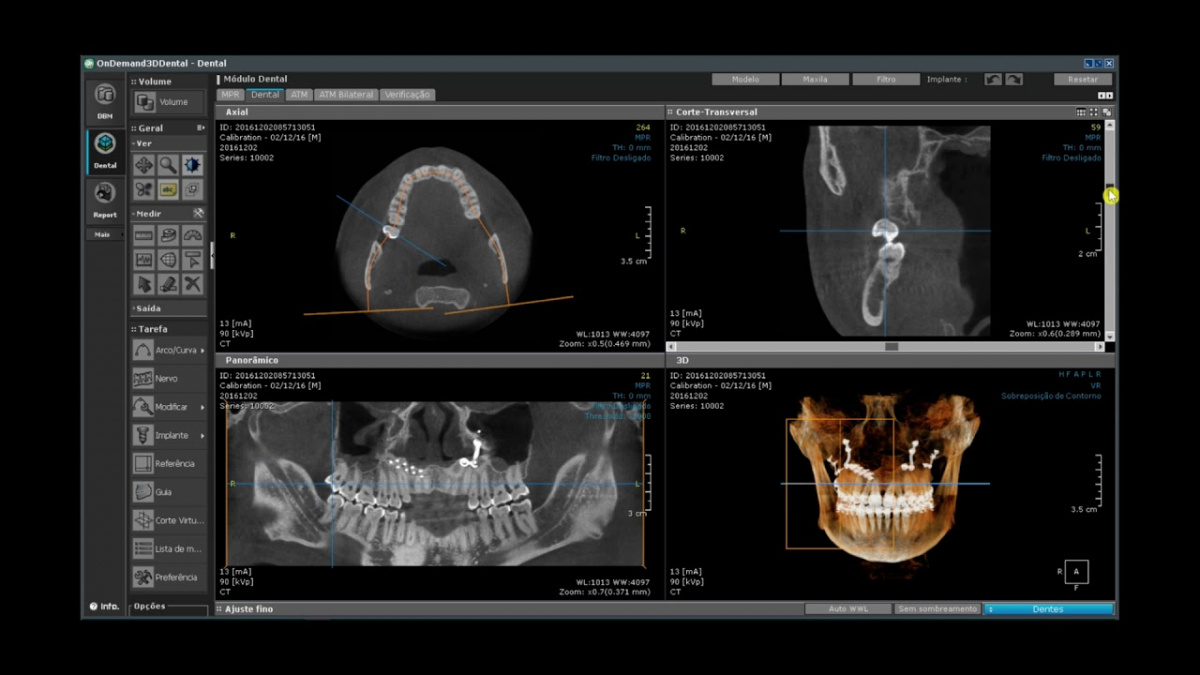

Немаловажным, а может главным вопросом, является универсальность программы-просмотровщика, в которой будут работать врачи-стоматологи. У Papaya 3D есть два варианта программ: Triana и OnDemand3D. Оба просмотровщика обладают схожим интерфейсом и имеют самые важные опции, а именно:

• режим MPR (многоплоскостная реконструкция). Именно здесь выстраивается интересующий участок челюсти или зуба для анализа.

• панорамный реформат. Возможность постройки классической и сегментарной панорамы позволяет продемонстрировать план лечения пациенту, а также оценить расположение анатомических структур на боковых кросс-секциях.

• модуль дентальной имплантации. Возможность виртуальной установки дентального имплантата с анализом окружающей костной ткани. В библиотеке представлен широкий спектр имплантологических систем с индивидуальной прорисовкой имплантата.

• выделение нижнечелюстного канала позволяет продемонстрировать расположение важного анатомического образования и определить зону безопасности при проведении лечения.

• функции плотности, линейных измерений и угла – необходимы для получения полноценной информации для последующего лечения.

• 3D режим – показывает трехмерную модель челюсти с целью определения аномалий, деформация, а также визуализации виртуальных имплантатов.

Таким образом обе программы являются простыми в пользовании, но обладающими обширным спектром возможностей для диагностики любыми специалистами-стоматологами. В данные программы происходит загрузка классических файлов DICOM 3.0, которые являются общепринятым форматом записи данных пациента. Это важный момент, так как позволяют врачу, имеющему полную версию программы загружать даже сторонние исследования и просматривать их в этих программах. Простота в освоении этих программ позволяет даже специалисту, не работающему раннее с этими программами, быстро адаптироваться и получить качественную информацию. Возможность выгрузки STL-файла дополнительно создает возможность интегрировать данные с цифровым ортопедическим протоколом.